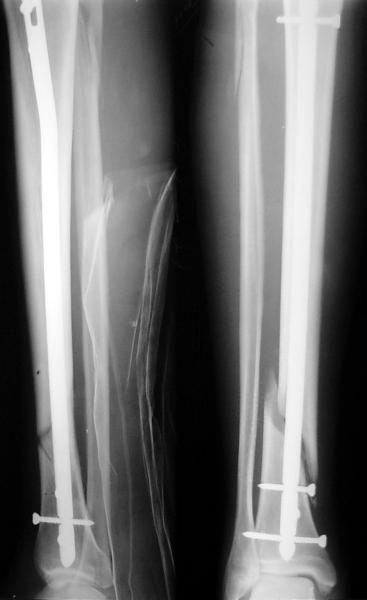

Ok. А также и следующий, в 3 месяца.

Это наглядная демонстрация возможности ранней полной нагрузки при нестабильном по оси повреждении, причем не в самых благоприятных механических условиях - при плохом сопоставлении, со слабым фиксатором.

Сверху - один статический винт, а снизу - три. Что раньше сломается? Конечно, он потом и нижние сломал, и Вы правы, если бы верхний динамичесий винт уже уперся бы в нижний край отверстия, будь гвоздь подлинее, перфорировал бы сустав как пить дать.

Как я уже говорил, мы сделали выводы из этого и других подобных случаев. Очевидно, решений проблемы два - либо уменьшить нагрузку, либо увеличить прочность фиксатора. Первое решение работает не со всеми больными, так что пошли по второму пути - мы больше не используем гвозди с запирающими винтами диаметром 4 мм.